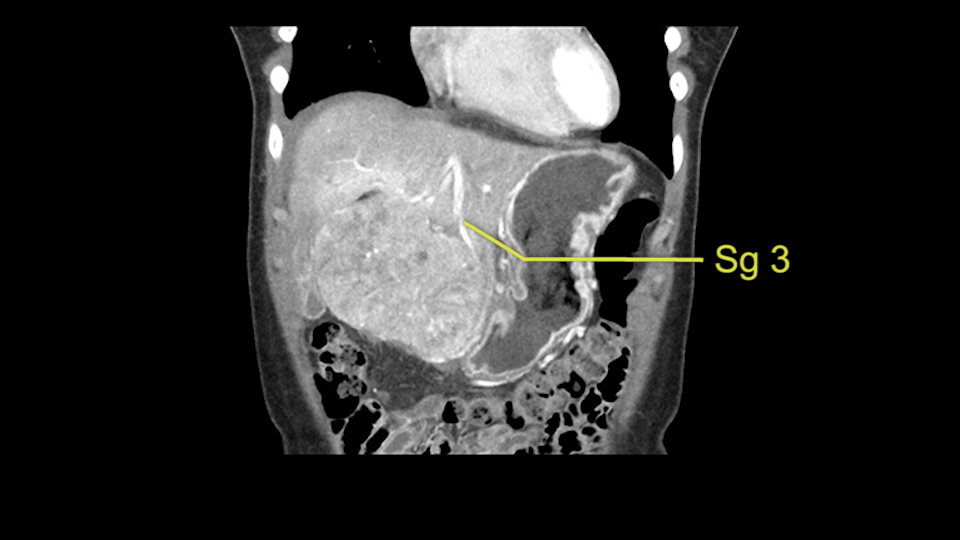

As I review the CT scan, we have both arterial and venous phases, the tumor is obvious. But I’ll start by saying that the liver itself does not appear to be cirrhotic to my eye. It’s got a normal contour and allied to that, that I do not see evidence of portal hypertension. The spleen is normal, there’s no collateral vessels. The tumor itself, I measured maximally at about 11 centimetres in diameter and I’m told the alpha fetoprotein is very high (over 10000), which is entirely consistent with this being a solitary hepatocellular carcinoma that is very exophytic. It seems to emanate off the inferior margin of Segment 3 (because that’s the falciform). I’ll start by saying that this is not transplantable. The tumor exceeds our guidelines for transplantation, but it's likely resectable based on normal liver and no portal hypertension.

So the issue with regards to resection. A left sided tumor. I believe I can see the falciform ligament right here so we’re looking at a resection of Segments 2, 3 of the left lobe of the liver. The left portal vein is right there. I think we’ll be wiser to take the left portal vein and therefore get well into Segment 4 and do a left hemihepatectomy. Certainly, one does not need to take the middle hepatic vein; it’s miles from the tumor.

We note that the tumor is pushing on the gallbladder but I think that’s probably external for the most part. I think that’s extrahepatic. I believe that Segment 4b is probably free of tumor. I’d have to say that it's tempting, particularly looking at the coronals, to consider a very limited resection. Where you’d just chip it off the bottom of Segment 3 and do a limited Segment 3 resection. I’d be concerned about the oncologic margins. I believe that the best oncologic operation will be to take the left portal vein to get this. Certainly, she’s got plenty of liver and she’d be able to sacrifice Segments 2-3 of the left lobe of the liver. It’s not necessary to take too much of thus of Segment 4a. But once one takes the portal vein, that will be compromised. So I would do a left hemihepatectomy on this woman.

The other thing I would do in this case is to certainly to assess the coronal phase as we can see in the coronal phase, this tumor looks like it's growing from Segment 3, and again I don’t think there’s involvement of the right side of the liver or even on Segment 4.